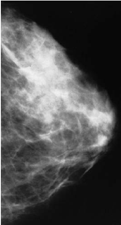

An example of a normal mammogram. Each woman’s mammogram may look a little different because all breasts are a little different.

You will stand in front of a special X-ray machine. A technologist will place your breast on a clear plastic plate. Another plate will firmly press your breast from above. The plates will flatten the breast, holding it still while the X-ray is being taken. You will feel some pressure. The steps are repeated to make a side view of the breast. The other breast will be X-rayed in the same way. You will then wait while the technologist checks the four X-rays to make sure the pictures do not need to be re-done. Keep in mind that the technologist cannot tell you the results of your mammogram. Each woman’s mammogram may look a little different because all breasts are a little different.

Having a mammogram is uncomfortable for most women. Some women find it painful. A mammogram takes only a few moments, though, and the discomfort is over soon. What you feel depends on the skill of the technologist, the size of your breasts, and how much they need to be pressed. Your breasts may be more sensitive if you are about to get or have your period. A doctor with special training, called a radiologist, will read the mammogram. He or she will look at the X-ray for early signs of breast cancer or other problems.